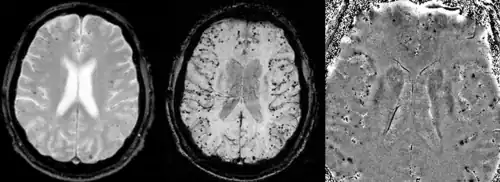

A AAC só pode ser definitivamente diagnosticada por uma autópsia (post-mortem).[25] As biópsias podem desempenhar um papel no diagnóstico de casos prováveis.[26] Quando não há tecido disponível para biópsia, os critérios de Boston são usados para determinar casos prováveis de AAC a partir de dados de ressonância magnética ou tomografia computadorizada. Os critérios de Boston exigem evidências de múltiplas hemorragias lobares ou corticais para rotular um paciente como provavelmente portador de AAC.[25] A imagem ponderada por suscetibilidade foi proposta como uma ferramenta para identificar microhemorragias relacionadas à AAC.[27]

A angiopatia amiloide cerebral pode se apresentar com hemorragia intracerebral lobar ou micro sangramentos no cérebro. O sangramento geralmente ocorre nas superfícies do cérebro, em contraste com a hemorragia intracraniana devido à pressão arterial elevada que ocorre em locais profundos do cérebro, como os gânglios basais e a ponte. No sangramento intracerebral lobar, a tomografia computadorizada (TC) mostraria uma área de hemorragia hiperdensa e um odema hipodenso ao redor do local da hemorragia.[17]

A sequência de RM de eco de gradiente e a imagem ponderada por suscetibilidade (SWI) são úteis na detecção de micro sangramentos e deposição de ferro no córtex cerebral (siderose superficial cortical).[17] Outros indicadores de RM de AAC incluem hiperintensidades de substância branca e afinamento cortical.[28]